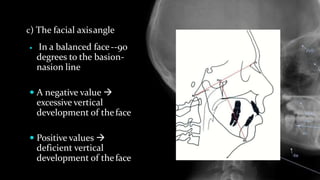

 In a balanced face--90

degrees to the basion-

nasion line

 A negative value 

excessive vertical

development of theface

 Positive values 

deficient vertical

c) The facial axisangle